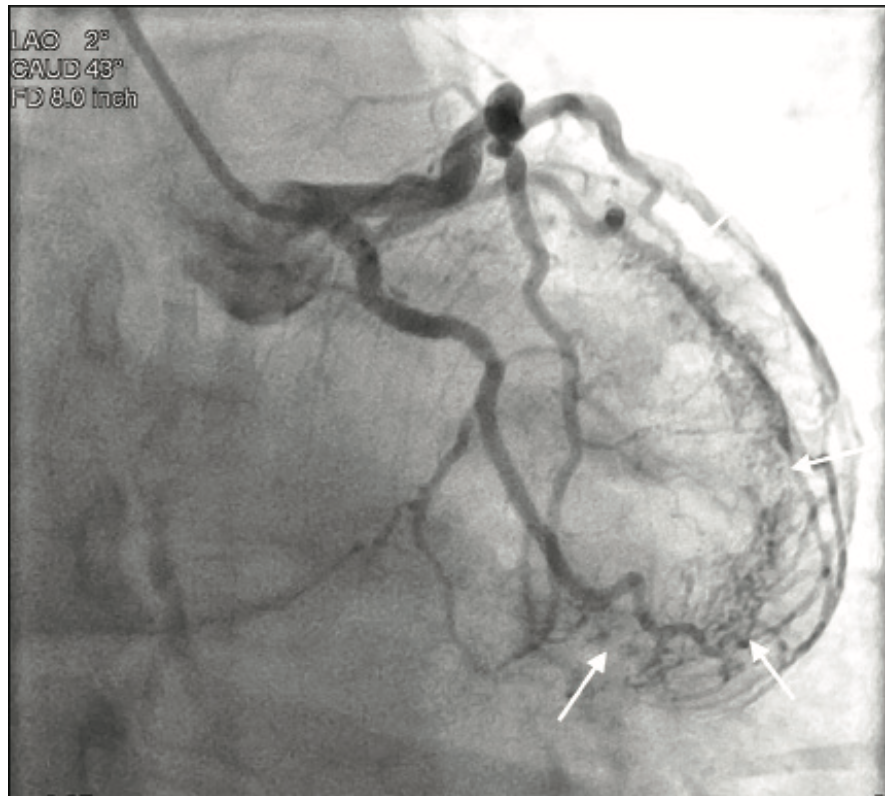

Video 2. Visualization of the apical and anterior walls of the ventricle.

Coronary angiography revealed no significant coronary artery disease, with only a minor lesion in the proximal right coronary artery. Left ventriculography was performed using a power injector. The patient had an approximate ejection fraction of 60% and there was no angiographic evidence of regurgitation. Following coronary angiography, the patient underwent an echocardiogram to further investigate the systolic murmur. No significant findings were discovered; however, a bicuspid aortic valve was noted, a congenital anomaly occurring in 1-2% of patients.1 Although the coronary arteries showed no significant disease, there was significant capillary blushing during injections of the left coronaries. A closer review of the images showed the blushing originating from a diagonal branch of the left anterior descending artery with a direct connection to the interior of the left ventricle, effectively providing a simultaneous coronary angiogram and ventriculogram.

Thebesian veins are generally found incidentally during coronary angiography2 and are the remnant of nutrient supply pathways in the embryonic heart3. In this case, the vessels provide a direct connection from the epicardial coronary arteries into the left ventricle. Although Thebesian veins are a rare angiographic find and the clinical effects are not entirely clear, they can make for very dramatic and interesting angiography.